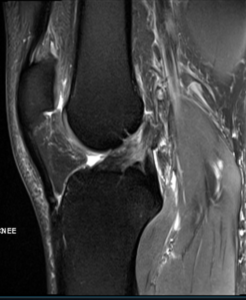

Diagnosis

An ACL injury can be diagnosed with a thorough physical examination of the knee and diagnostic tests such as X-rays, MRI scans and arthroscopy. X-rays may be needed to rule out any fractures. In addition, your doctor will often perform the Lachman’s test to see if the ACL is intact. During a Lachman test, knees with a torn ACL may show increased forward movement of the tibia and a soft or mushy endpoint compared to a healthy knee.

Pivot shift test is another test to assess ACL tear. During this test, if the ACL is torn, the tibia will move forward when the knee is completely straight and as the knee bends past 30° the tibia shifts back into correct place in relation to the femur.